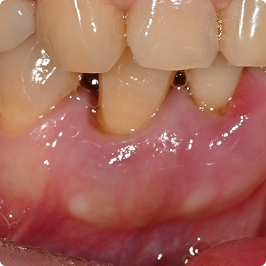

02

약해진 잇몸과 뼈, 잇몸 재생 치료로 지켜낸 편안한 일상

치료 전

치료 후

치료 내용

• 이전에 치료받은 치아의 잇몸이 내려가서 빈공간에 잦은 염증

• 치주수술 + 엠도게인 적용으로 잇몸 재생 유도

• 치료 후 잇몸과 잇몸 뼈가 재생되어 빈 공간이 채워짐